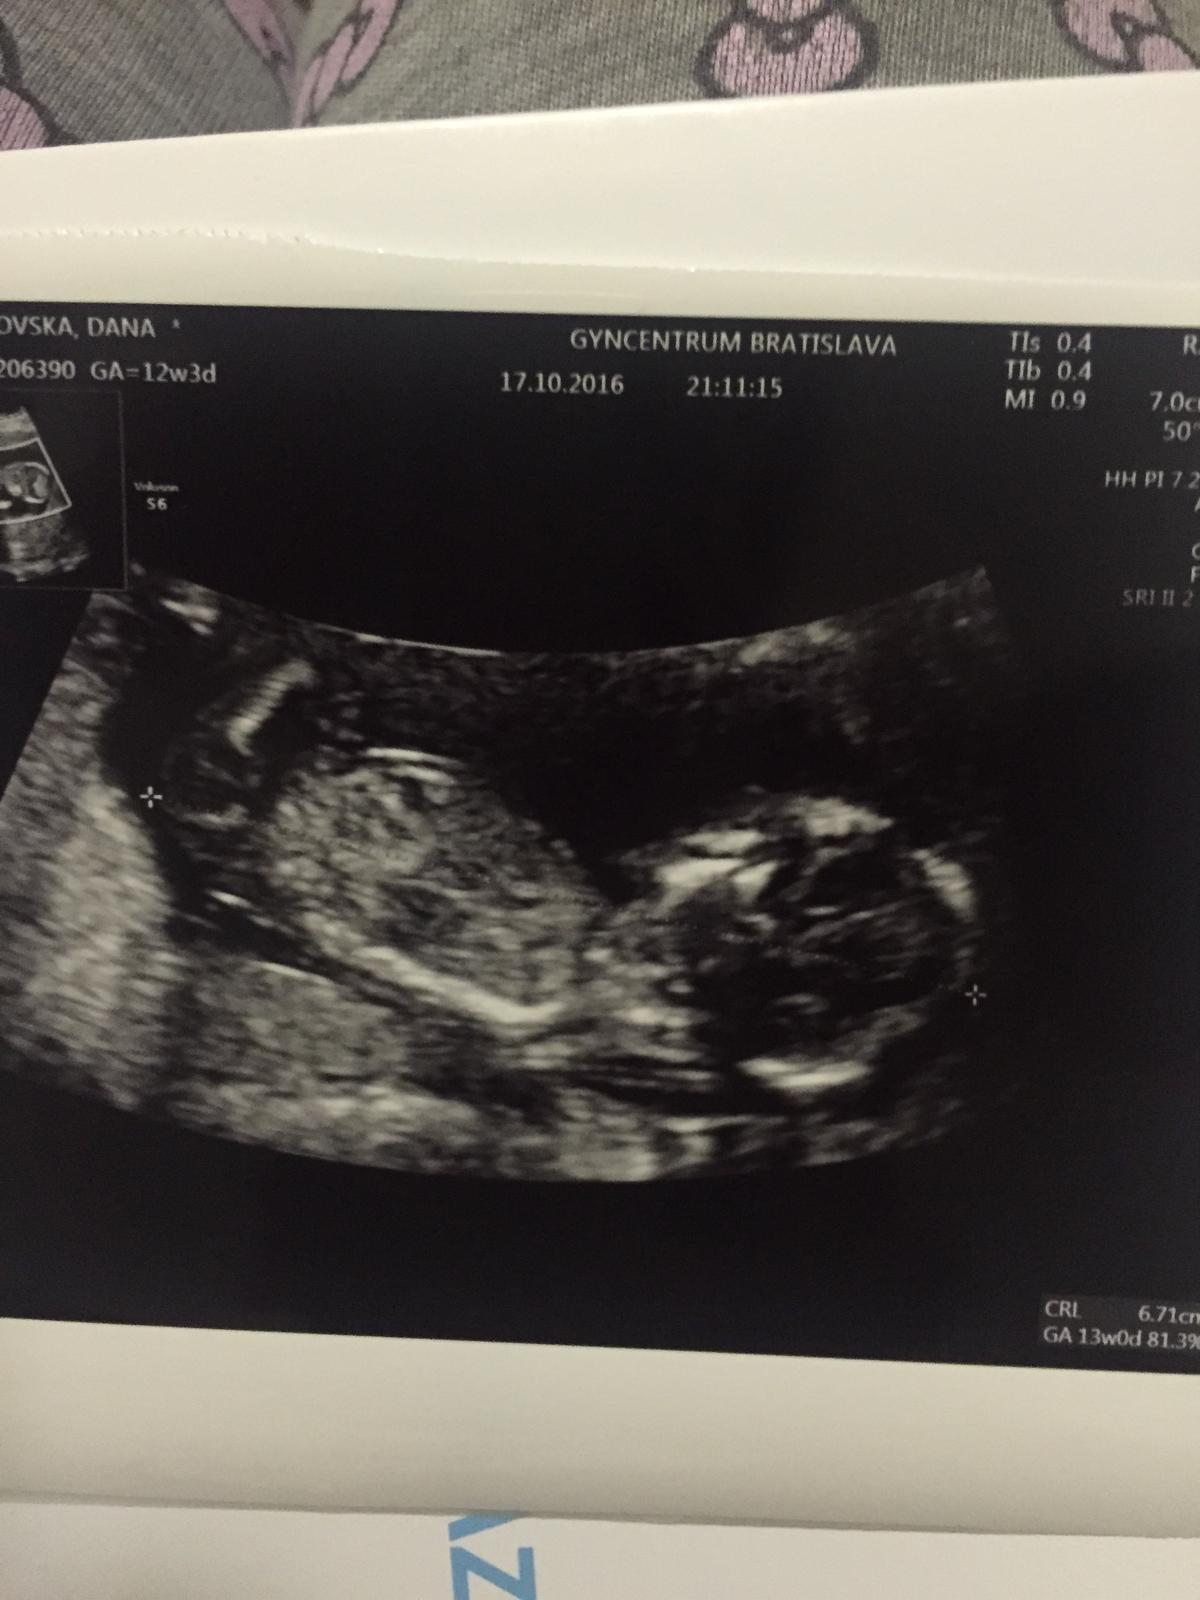

A dnes sono. Podla pm 12+3 ale podla sona 13+0, nt v poriadku, nosova kosticka bola, z krvi vysledky ok. Pohlavie, ze on netipuje. Povie mi az si bude isty.